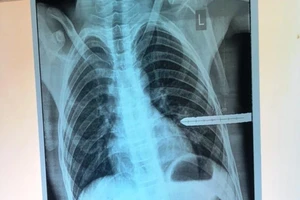

Cứu bé trai 13 tuổi bị thanh sắt dài đâm thủng phổi